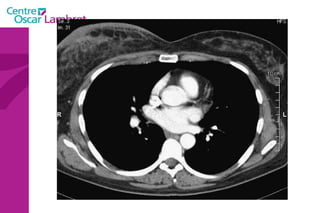

Le coeur  comprend quatre cavités :  deux cavités droites, formées par l’oreillette (ou atrium) et le ventricule droit.  deux cavités gauches, formées par l’oreillette (ou atrium) et le ventricule gauche.  Les cavités droite et gauche sont totalement séparées par une cloison (septum).  Ces cavités sont connectées à des veines et des artères qui conduisent le sang venant ou partant du coeur.  L’appareil circulatoire

Les 2  atriums  ont un petit diverticule : les auricules Le cœur repose sur le diaphragme et est situé au niveau de la partie antérieure et inférieure du médiastin. Le coeur est bordé latéralement par les poumons qui le recouvre partiellement. Les 4 cavités du coeur sont limitées par des sillons. Le  sillon coronaire le sillon inter atrial  Le sillon inter ventriculaire ou septum L’appareil circulatoire

La partie droite  assure la circulation du sang riche en CO² recueilli par les veines caves (sup et inf) :  ce sang aboutit dans l’oreillette droite et est éjecté dans le ventricule droit. L’oreillette et le ventricule droits communiquent par l’orifice auriculo-ventriculaire droit, lequel est obturé par la valvule tricuspide, empêchant le retour de sang du ventricule vers l’oreillette. Le sang est ensuite éjecté dans l’artère pulmonaire, l’obturation étant assurée par la valvule sigmoïde.  L’appareil circulatoire

La partie gauche  assure la circulation du sang oxygéné recueilli par les veines pulmonaires. ce sang aboutit dans l’oreillette gauche et est éjecté dans le ventricule gauche.  L’oreillette et le ventricule gauches communiquent par l’orifice auriculo-ventriculaire gauche, lequel est obturé par la valvule mitrale.  Le sang est ensuite éjecté dans l’artère aorte, l’obturation étant assurée par la valvule aortique.  L’appareil circulatoire

L’appareil circulatoire L’ aorte  est la plus grande artère du corps.  Elle part du ventricule gauche du coeur et apporte notamment du sang oxygéné à toutes les parties du corps via la circulation. Elle est divisée en aorte thoracique et aorte abdominale. L’aorte thoracique  comprend trois segments : l'aorte ascendante, horizontale et descendante.